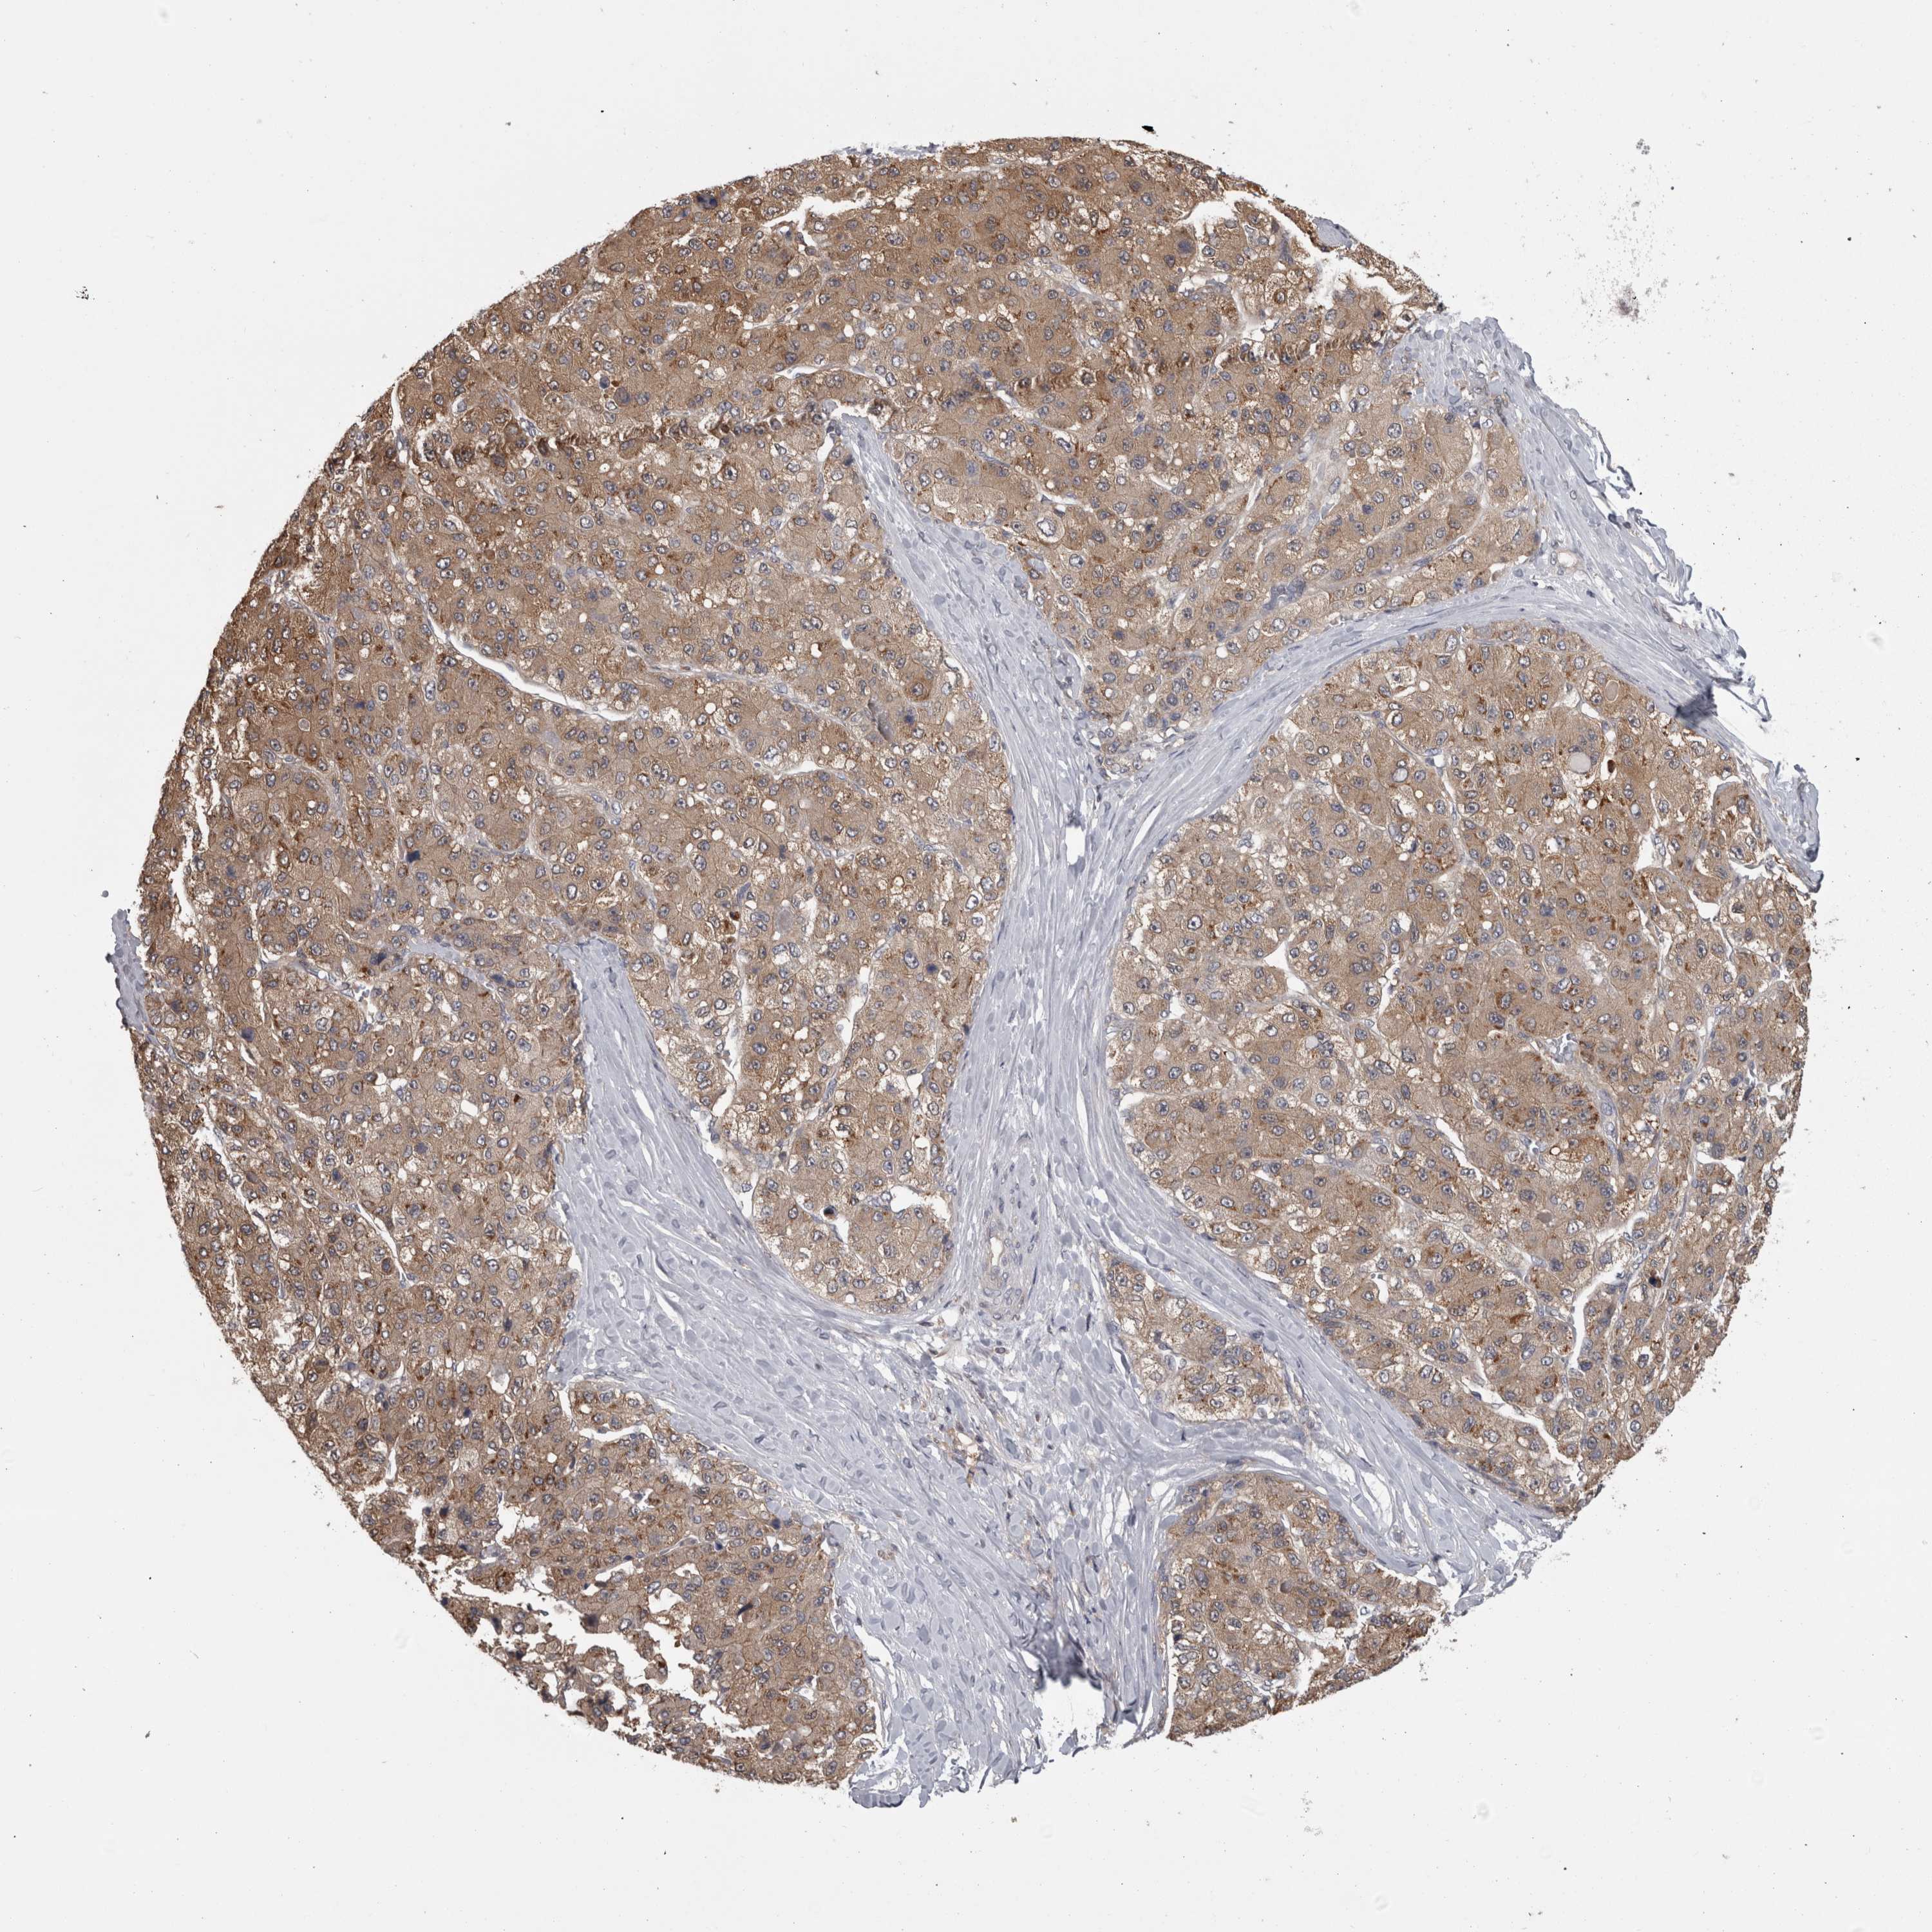

LIVER CANCER - Protein expressioni

A mouse-over function shows sample information and annotation data. Click on an image to view it in a full screen mode. Samples can be filtered based on level of antibody staining by selecting one or several of the following categories: high, medium, low and not detected. The assay and annotation is described here.

Note that samples used for immunohistochemistry by the Human Protein Atlas do not correspond to samples in the TCGA dataset.

Antibody stainingi

Antibody staining in the annotated cell types in the current human tissue is reported as not detected, low, medium, or high, based on conventional immunohistochemistry profiling in selected tissues. This score is based on the combination of the staining intensity and fraction of stained cells.

Each image is clickable and will lead to virtual microscopy that enables deeper exploration of all samples and also displays staining intensity scores, fraction scores and subcellular localization as well as patient and tissue information for each sample.

Antibody HPA026681

Staining

High

Medium

Low

Not detected

Intensity

Strong

Moderate

Weak

Negative

Quantity

>75%

75%-25%

<25%

None

Location

Nuclear

Cytoplasmic/membranous

Cytoplasmic/membranous,nuclear

Cholangiocarcinoma

Carcinoma, Hepatocellular, NOS